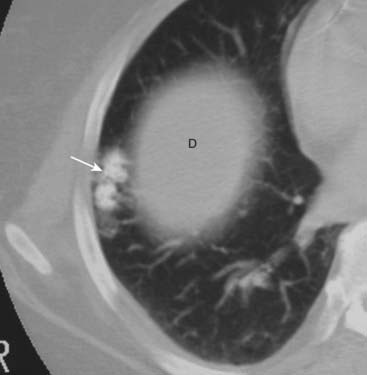

image Hamartomas. Peripherally located lung tumors of disorganized lung tissue that characteristically contain fat and calcification on CT scan. The classical calcification of a hamartoma is called popcorn calcification (Fig. 12-15).

Figure 12-15 Hamartoma of the lung.

Hamartomas of the lung are peripherally located tumors of disorganized lung tissue that classically contain fat and calcification on CT scans. The classical calcification of a hamartoma is called popcorn calcification (solid white arrow). The small island of soft tissue in the middle of the right lung (D) is the uppermost part of the right hemidiaphragm.